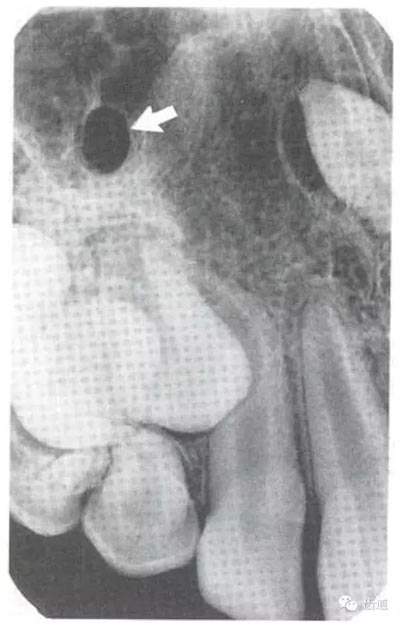

3)頦孔:

位于前磨牙根尖區(qū)域,為一大致圓形密度低的影像。頦孔位置變異大,多位于第二前磨牙根尖稍下,注意與根尖周病變區(qū)別,其要點(diǎn)是牙周膜及其骨硬板是否連續(xù)不斷。

5)下頜管:

位于磨牙牙根尖下方,呈寬約為0.4cm凹面向下邊緣整齊的帶狀密度低的影像,其兩側(cè)有密度高的線條狀影像,為下頜管骨密質(zhì)